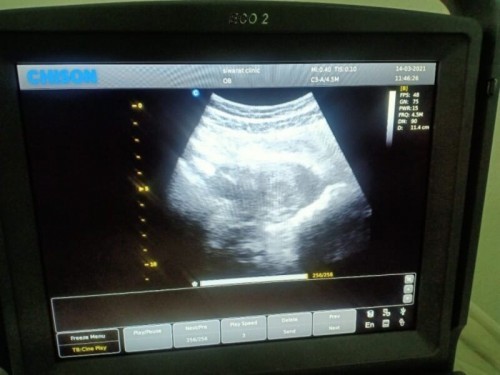

ตอนไปฝากครรภ์5w ซาวด์หน้าท้องก็ไม่เห็นอะไรนะคะ หมอเลยเปลี่ยนเป็นซาวด์ทางช่องคลอดถึงเห็นถุงตั้งครรภ์ค่ะ แต่หมอยังไม่ให้ฝากต้องรอเห็นหัวใจก่อน พอซาวด์อีกรอบตอน7w ก็เห็นหัวใจน้องแล้วถึงได้ฝากค่ะ แต่ตอน7wก็ยังต้องซาวด์ช่องคลอดอยู่เลย เพราะทำที่หน้าท้องแล้วมองไม่เห็น หมอว่าหน้าท้องเราอาจจะหนานิดหน่อยเลยทำให้ไม่เห็นค่ะ

Đọc thêmเราไปหาหมอเร็วเหมือนกัน ได้ไปใหม่อีก 1 อาทิตย์ต่อมา เพราะไม่ค่อยเห็นเด็กและตรงจการเต้นหัวใจไม่ได้ พอผ่านไป 1 อาทิตย์ไปใหม่ก็ยังไม่ค่อยเห็น เลยใช้เครื่องสอดช่องคลอดดูคราวนี้ทั้งตัวทั้งเสียงเห็นชัดเลย ไปตอนสัก 6-7 week

ซาวจร้าหมอบอกหน้าจะ3-4วีคไม่เจออะไรเลยเจอแต่ผนังมดลูกหนาขึ้น อีกอาทิตย์นัดใหม่ไปซาวเจอเเต่ถุง อีก1เดือนนัดใหม่คราวนี้เห้นชัดตัวใหญ่ เสียงหัวใจปกติ รออีกหน่อยนะค่ะเเม่ เด่วก้เห้นชัดคะ

ไปฝากครรภ์มาเมื่อวาน22/3/64 เห็นคุณแม่ท่านนึงท้องออกเยอะแต่ซาวด์ไม่เห็นหัวใจน้อง ตัวเองท้องออกน้อยแต่เจอหัวใจและที่บ้านบอกน้องตัวใหญ่ 7w+2ค่ะ

เหมือนกันค่ะ ครั้งแรกไปหาหมอซาวน์ตอน 4w ตอนนั้นเห็นถุงครรภ์ หมอไม่ยืนยันค่ะ อาจจะท้องลม หมอนัดอีกทีตอน 6w เห็นน้องและได้ยินเสียงหัวใจค่ะ

เรารู้ตัวตอน 7 วีคค่ะ ไปคลินิกให้คุณหมอซาวด์ให้ ทั้งแบบหน้าท้องและช่องคลอด ก็พบถุงการตั้งครรภ์เลยค่ะ เห็นหัวใจเต้นแล้ว ☺️